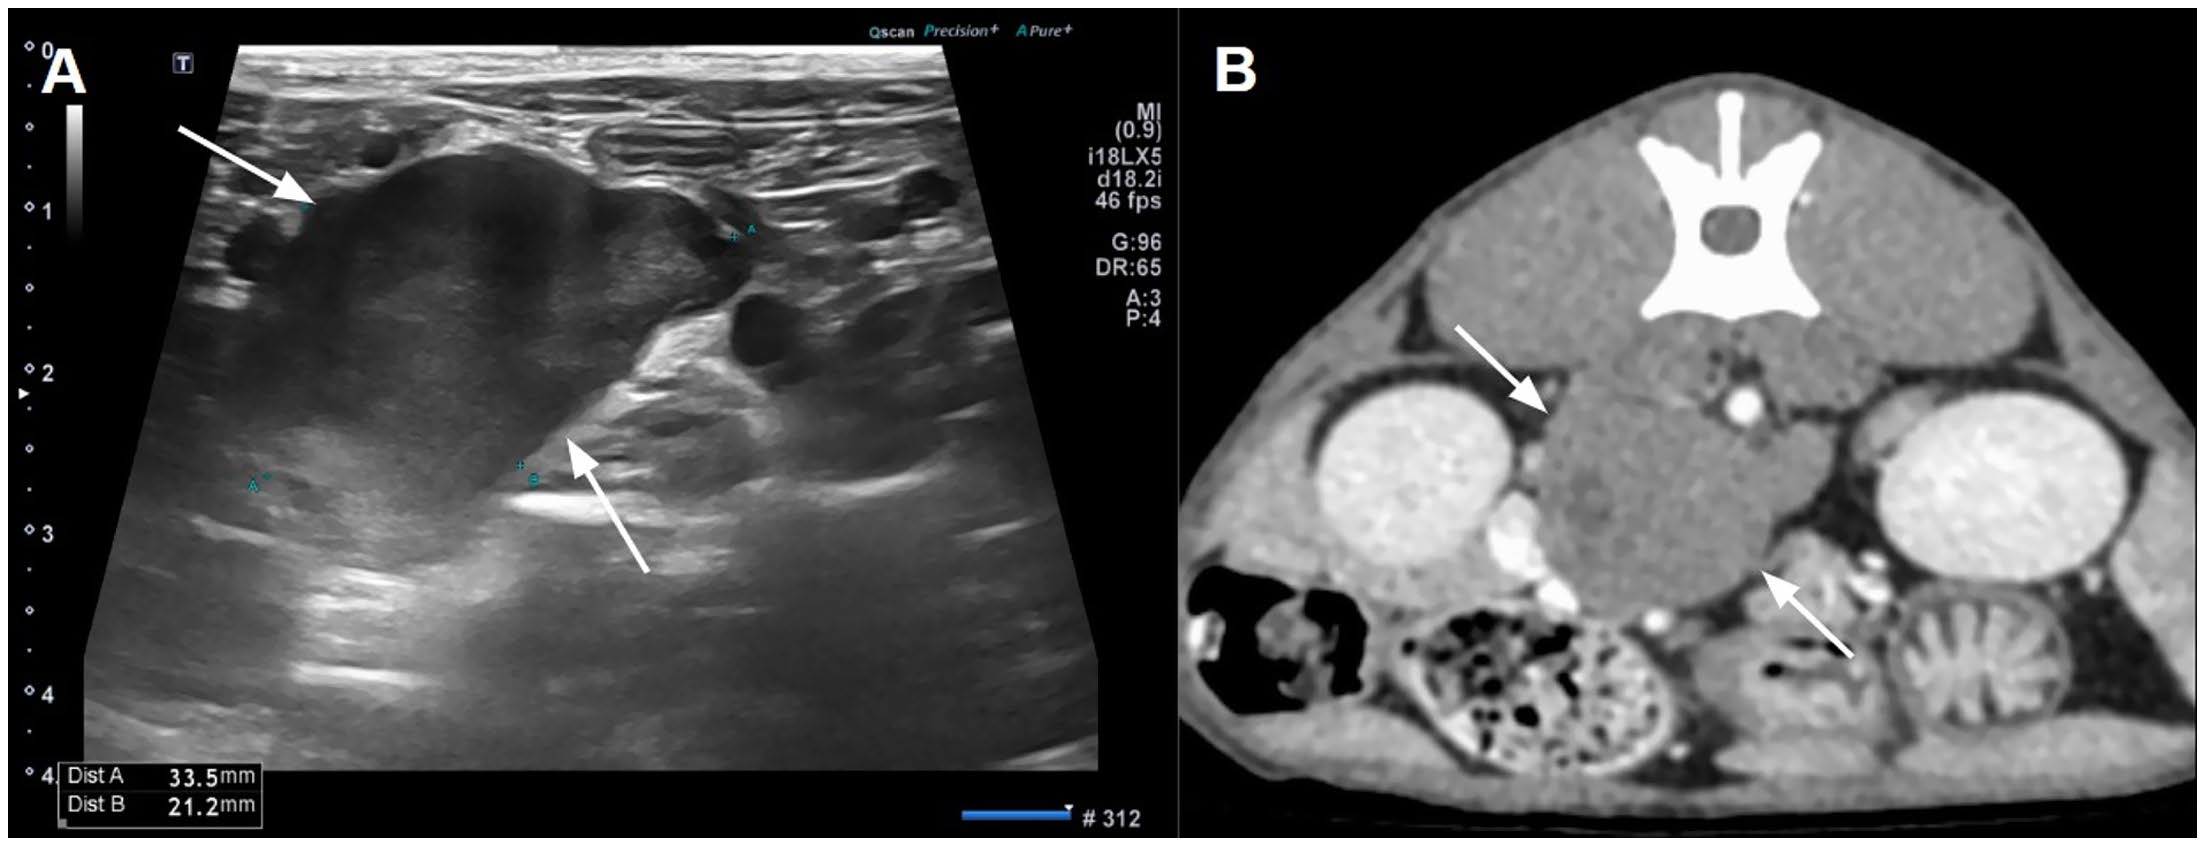

超声观察到一个轻度不均匀的低回声肿块紧邻两侧肾上腺(下图A)。腹部CT显示一个不规则的、软组织密度的、腹膜后肿块(3×2.5×3.5厘米),紧邻两侧肾上腺(下图B)。该肿块与肾上腺相比显示出轻度对比增强(约60-70 HU),而肾上腺约为150 HU。肿块内显示出一个无增强的囊内结构,并对邻近的后腔静脉和门静脉造成压迫和移位。观察到空肠、肝脏和脾脏淋巴结轻度肿大,被认为是反应性淋巴结肿大。胸部CT未发现显著异常。

↑ 腹部超声(A)和CT(B)显示在两侧肾上腺之间有一个低回声且轻度对比增强的肿块。肿块内显示出一个小的低密度区域,反映了囊性变性。

在影像学检查中,超声和CT揭示了一个位于肾上腺附近的不规则、轻度对比增强的腹膜后肿块。尽管这些影像学特征与以往报道的副神经节瘤部分一致,但缺乏特异性,因此需要结合病理学和免疫组化进行最终诊断。